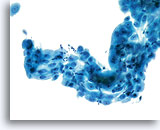

Lower Uterine Segment

With increased vigilance by providers to collect adequate specimens, aggressive sampling may result in the presence of cells from the lower uterine segment in cervicovaginal samples. Cells from the lower uterine segment generally present as a tissue fragment rather than individual cells or small groups of cells. The fragment has well ordered nuclei and nucleoli may be present. A folding over of the fragment on itself may cause a three dimensional appearance.